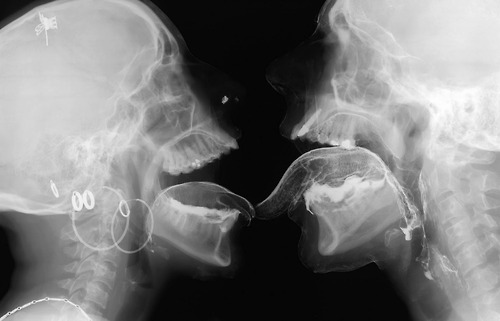

[…] Cuando el artista belga Wim Delvoye realiza imágenes por rayos X de un beso o de actos sexuales, imágenes X por medio de rayos X, no hace otra cosa que apropiarse estéticamente de técnicas científicas a veces de punta, reintroduce la «skiagrafía», excluida antiguamente por la filosofía, y, en la ciencia, lo concerniente al acto sexual, que ella excluye.

Podríamos evocar dos imágenes radiográficas de Wim Delvoye. Estas imágenes tomadas por rayos X, clasificables en la góndola de las imágenes X, poseen una fuerza de verdad extrema. Sin embargo, no donde uno cree, no donde uno ve. Al mostrar un beso o una felación, son para verlas, desde luego, como toda imagen, pero ellas muestran lo que no se ve a simple vista, el interior de los cuerpos en actividad. Ellas nos sitúan en un tiempo posterior al cine pornográfico. El valor del surgimiento del cine pornográfico, si ese valor existe, es en el fondo, haber mostrado algo, una parte de la anatomía que el cine jamás había mostrado, los órganos sexuales en actividad. Las imágenes de rayos X, al ir más allá de la anatomía, van más lejos: van al sexo bajo la piel. Por otra parte, si bien tales imágenes cumplen el sueño de la cámara pornográfica de mostrar desde lo más cerca posible, esto no produce exactamente una mayor excitación sexual. En verdad, las imágenes de Wim Delvoye tienden a mostrar una cosa que no se había visto nunca: cómo funciona el sexo. Sin embargo, debería decirse más bien que lo que estas imágenes muestran, es que no se lo ve. Más aún, que lo normal es que no se lo vea.

[…] Para más exactitud, yo diría que estas imágenes de rayos X, que es posible reunir con el dibujo anatómico de Leonardo en el que se representa el corte de un coito muestran sobre todo que hay algo que no se puede ver: cómo funciona el amor, cuál sería el secreto del sexo. Tal es su dimensión crítica. Ellas se dirigen también a los médicos y a todos para decir que la búsqueda de la transparencia del cuerpo es una fantasía, porque hay algo que jamás se podrá ver ni saber, y por lo tanto dominar: la relación sexual. Pueden ustedes radiografiar el cuerpo, autopsiar el cuerpo, volverlo todo lo transparente que quieran, pero jamás verán con sus ojos el secreto de la relación sexual; o mejor dicho, jamás verán la única verdad que hace saltar los ojos: que no hay nada que ver, que no hay secreto. Esto es lo que, al fin de cuentas, resiste definitivamente a la voluntad del amo de que «eso funcione».